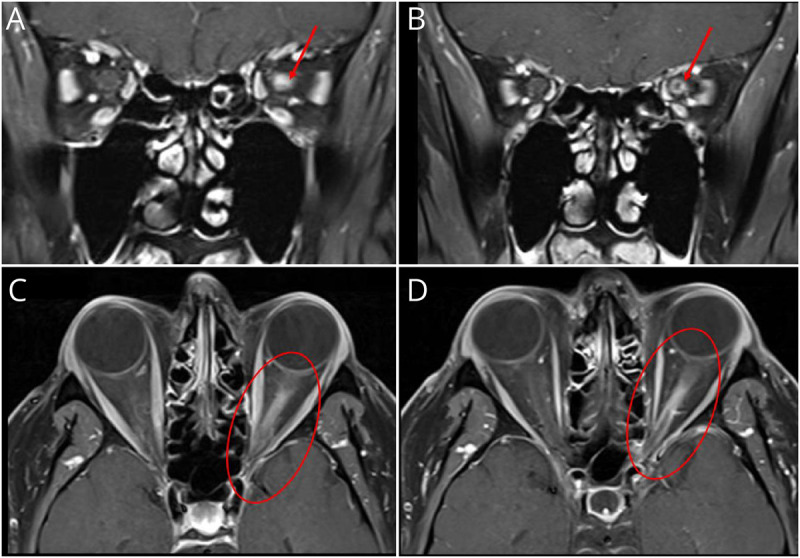

A 46-year-old man presented with progressive painful monocular vision loss and left leg paresthesias. Workup demonstrated multifocal demyelinating lesions and CSF-restricted oligoclonal bands. He was diagnosed with multiple sclerosis (MS), but follow-up testing was notable for positive myelin oligodendrocyte glycoprotein-immunoglobulin G (MOG-IgG). We discuss implications and clinical considerations for MOG-IgG positivity in MS.